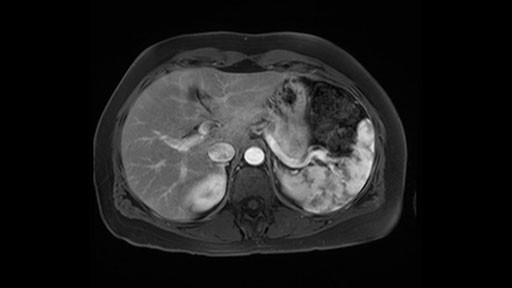

In reviewing this patient’s CT scan, first of all, the lesion is again cystic with a very thin wall. I anticipate that it will be delicate and potentially friable. And therefore the risk of rupture exists and we need to be very careful in how we handle the pancreas and the tumor throughout the procedure.

The lesion itself is quite adjacent to and abuts the splenic vein and therefore we need to anticipate that these two structures will be intimately related and possibly impossible to separate between the two.

The lesion also is quite posterior. While the plane between the cyst and the left adrenal gland is often preserved, we do have to pay attention here so that we remain in the right plane and maintain our margin here. Occasionally in these cases, en bloc adrenalectomy needs to be performed.

Hi my name is Carol-anne Moulton, I’m one of the surgeons here at TGH and an associate professor in the department of surgery. So I’ve had the ability to look at the MRI of this case that I’ve been asked to comment on. It has a mucinous or what appears to be a mucinous cystadenoma in the tail of the pancreas. To me, it looks like a pretty straightforward case. I agree with the decision to remove the tumor or cyst, give that it is unilocular and large and likely a mucinous cystadenoma. My preferred method of doing this particularly in a benign situation would be a laparoscopic distal pancreatectomy with or without the spleen.

The second slowing down moment or consideration I give to a distal pancreatectomy is the anatomy of the portal vein and the splenic artery. And so I look here and the anatomy is pretty straightforward. The splenic vein comes off normally and runs behind the pancreas and I can see the artery superior to that, again coming off in a normal manner from the celiac axis. So those two things, the portal vein and the splenic artery will be taken normally in this procedure.

The preoperative MR is very very important; any scan for that matter. Whether it is a pancreatic protocol CT scan or the MR as presented, the diagnostic imaging plays a very big role. And with this we see that it’s a very well-defined cystic focus in the body of the pancreas. Although there are septal enhancements, very well demarcated, but there is no vascular involvement. However, the mass appears to be in contact with the splenic vessel, and the mass is also a little bit in touch with the left adrenal and also the loop of bowel. So looking at this, basing on the features, I think it’s probably a mucinous cystic lesion, it could possibly be a pseudocyst. But basing on the history, it appears like there is no history that would point out to a pseudocyst. And not an IPMN as well; I don’t see any side branches from the MRCP and the MR scan and although there is no axial T2 images available, and I truly find it easier to identify the septations on T2, and the hepatic cyst that is visible on this scan makes it hard to differentiate it from a simple or complex cyst which may be considered in a mucinous neoplasm with cystic or mucinous metastasis. Basically the contrast would help us in identifying the enhancing mural nodules or septations in the cysts. The MRCP is definitely helpful to identify if there is any side branch, if we are considering any IPMN.

So first, I'll show you the scan. Here's the traditional view, where you see the cyst, which is in the body of the pancreas. And you see over here, it's got a quite thick wall. And going a little bit back also, here you see a septation which is very important, because I think a septation is what separates this from, for instance, the pseudocyst of the pancreatitis. And also the location of the cyst you see here, abutting the adrenal gland and going down a bit more, it's also quite close to a bowel loop. So when thinking about this cyst: female, the location in the body of the pancreas, thick wall, septation, and as you can read in history, it was basically asymptomatic, so no signs of pancreatitis. So, this probably all points towards a mucinous cystic neoplasm.

Then the next thing to look at is the size. So until recently mucinous cysts would always undergo surgery. But with the recent new evidence based European guideline (2018)*, it’s a European guideline but it had all the world literatures involved, the cut-off for surgery is now actually four centimeter unless the cyst is smaller and patients have symptoms, for instance pain or pancreatitis, or whether there's a nodule. But for a asymptomatic mucinous cystic neoplasm, cut-off for surgery based on literature is now four centimeters. The risk of cancer in the cyst below four centimeters is lower than the risk of killing the patient by doing surgery. So I think that's a new addition to the guidelines and I think it's a very important one.